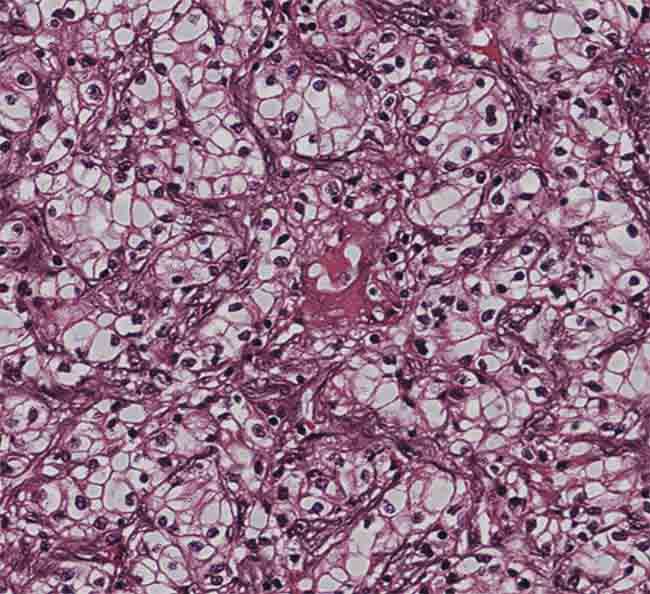

A virtually stained kidney tissue image showing compact nests and sheets of cells with clear cytoplasm and distinct membrane. Courtesy of the Ozcan Lab/UCLA.